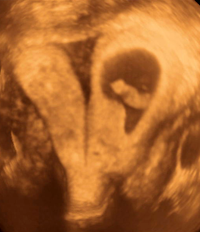

Myelomeningocele high resolution ultrasound.